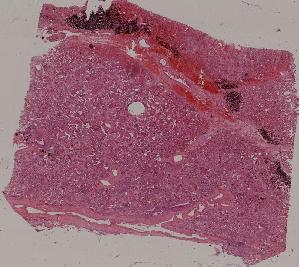

66. Active nodular cirrhosis of the liver

67. Inactive nodular cirrhosis of the liver

68. Biliary fibrosis